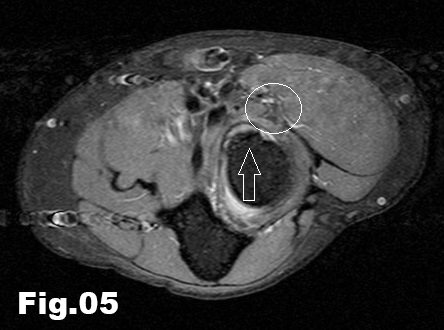

A 51-years-old healthy female, with no history of upper limb injuries, complained of an anterior and proximal left forearm tenderness associated with weakness of the extensor muscles of the forearm. An ultrasound scan was performed and demonstrated a thickened and hypoechoic posterior interosseous nerve (PIN) at the arcade of Frohse, with hypervascularization of the perineurium. In its deeper aspect, there was a subtle irregularity of the radial metaphysis (Fig1,2). The plain film showed a sessile irregularity of the anterior region of the metaphysis (Fig 3). Unenhanced MRI and CT scan were also performed. The CT scan showed the irregularity of the radius (Fig 4) and in the MRI (Fig 5), it was reported as an osteochondroma like metaphyseal lesion of the radius. Initial treatment included a corticosteroid injection around the PIN, but without decrease of symptomatology. The orthopedic surgeon then proceeded with an osteochondroma resection to release the PIN. The upper limb surgical team performed the surgery (Fig 6), and they found a thickened, hyperaemic PIN, adjacent to the osteochondroma (Fig 6,7). They resected the osteochondroma and debrided the PIN (Fig 8). The patient recovered full muscular strength and the tenderness progressively disappeared.

Fig 5: Axial PD and T1 weighted images, showing the relationship between the osteochondroma (arrow) and PIN (circle). Poor visualization of PIN and almost no presence of soft tissue oedema on the PD weighted sequence.